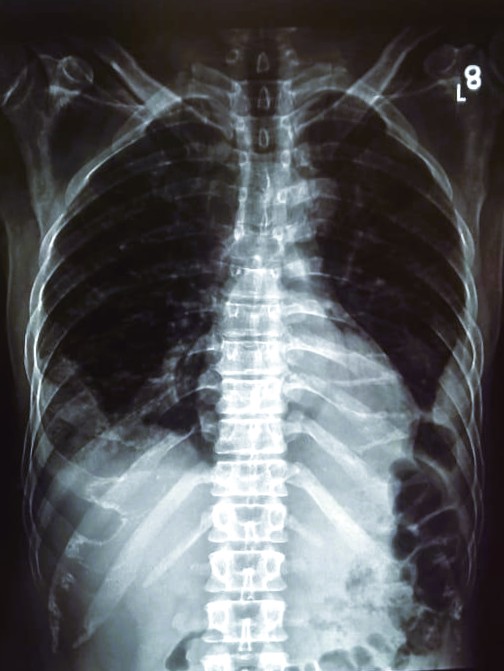

| 213 | IGGMC, Nagpur, Nagpur | P2 | 29-4259 | NARENDRA YADAV | Consent taken on Paper | 42 Yrs. |

Provisional Diag : Rt. SIDED LOCULATED PNEUMOTHORAX WITH Lt. ICD IN SINCE (15/11/24)

Final Diag : CLINICALLY DIAGNOSED TUBERCULSIS PLEURAL EFFUSION ON ATT (17/11/24) |

TB Case (Confirmed) | CXR: Rt. SIDED LOCULATED PNEUMOTHORAX Rt. U2+M2+L2 AND Lt. M2 CONSOLID? | Abnormality visible on x-ray |

View |

|||